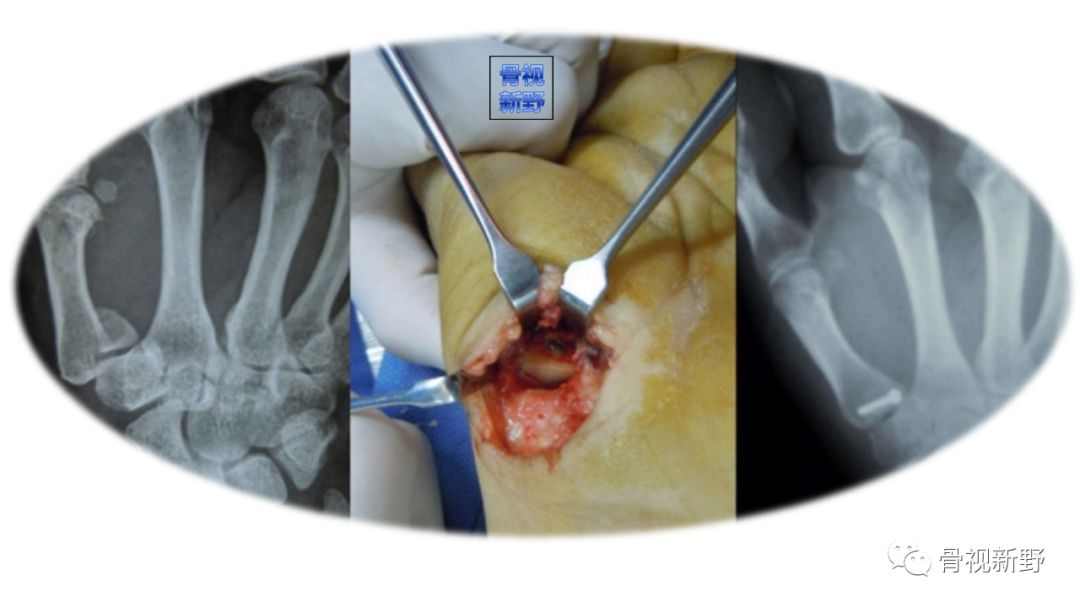

Bennett骨折是指第一掌骨基底部关节内部分骨折合并第一腕掌关节半脱位。由爱尔兰医生Bennett于1882年首先描述而得此名。

切开复位螺钉内固定

(ORIF using screw)

ORIF最早在1952年就有报道。

常用掌侧入路

ORIF螺钉内固定